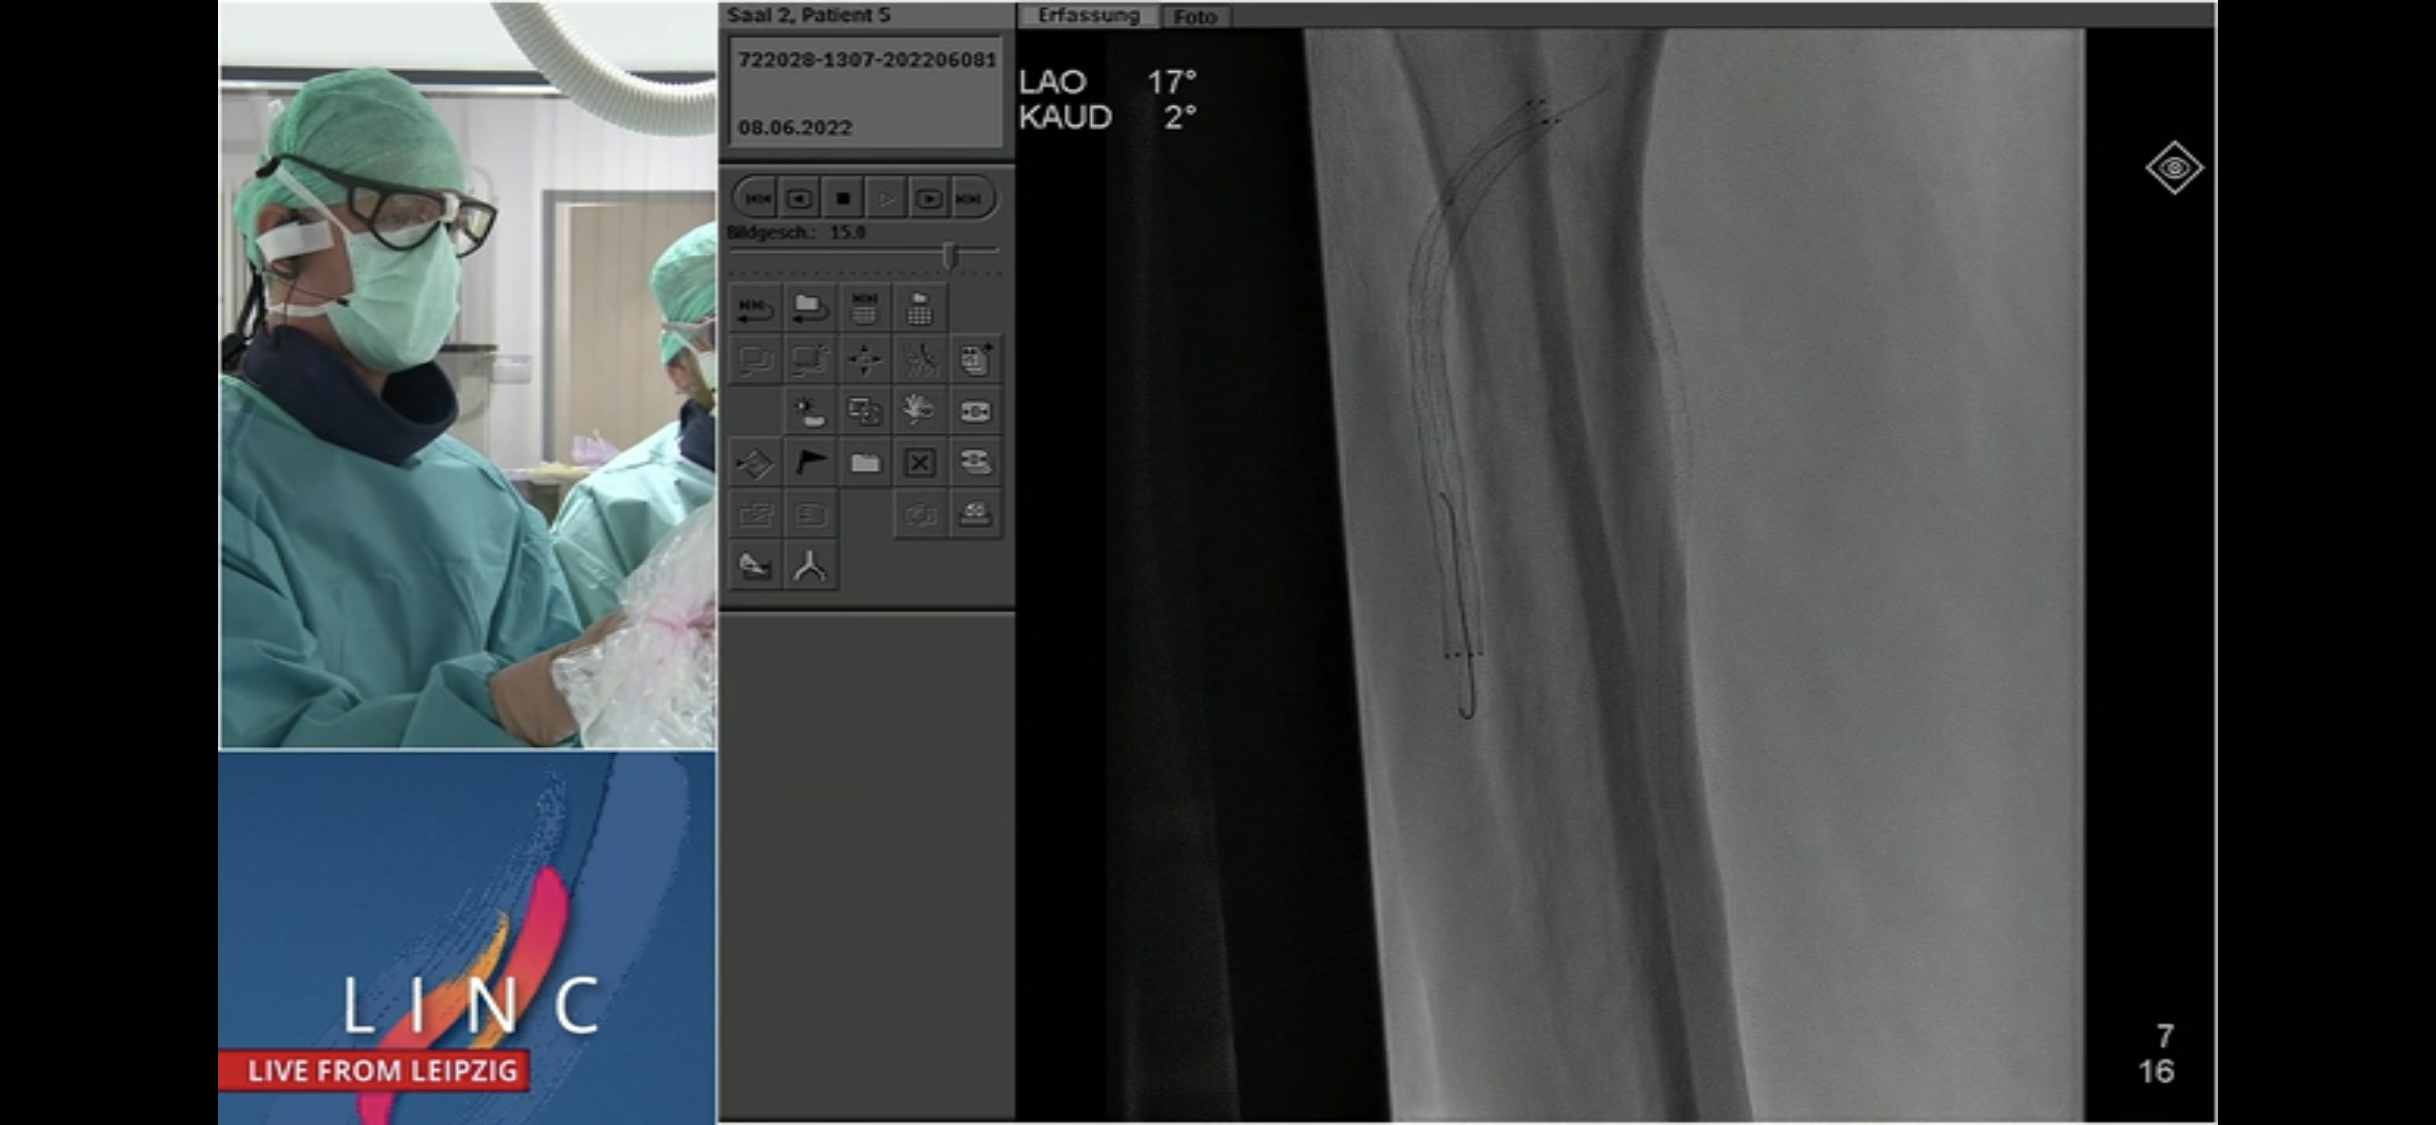

BTK heavyweights Weds 8.6.22 PM

First Schneider on TADV and Detour